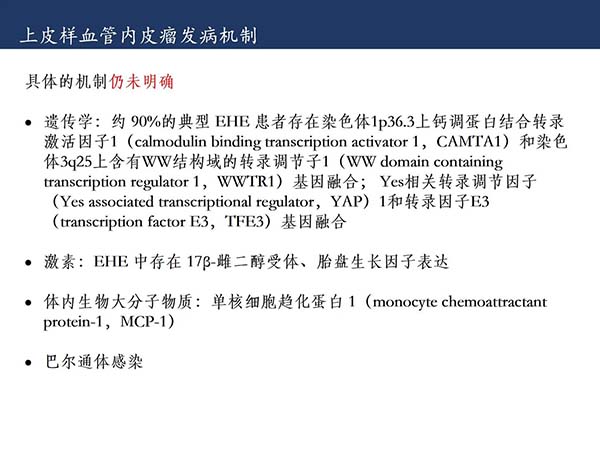

【杨柳科普】肺上皮样血管内皮瘤的影像表现